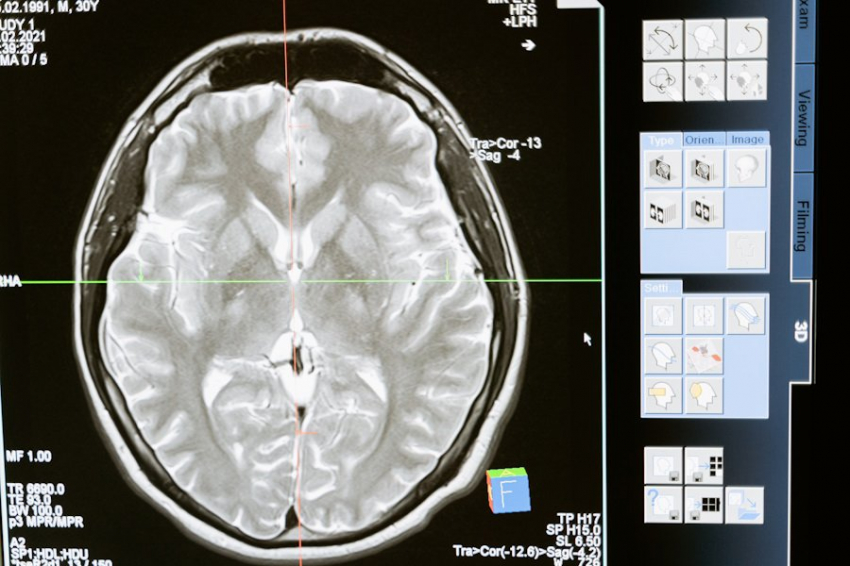

Фото из открытых источников

Исследование, организованное специалистами Научного института Сан-Раффаэле и Тулузского института инфекционных и воспалительных заболеваний, выявило корреляцию концентрации витамина D и активности рассеянного склероза.